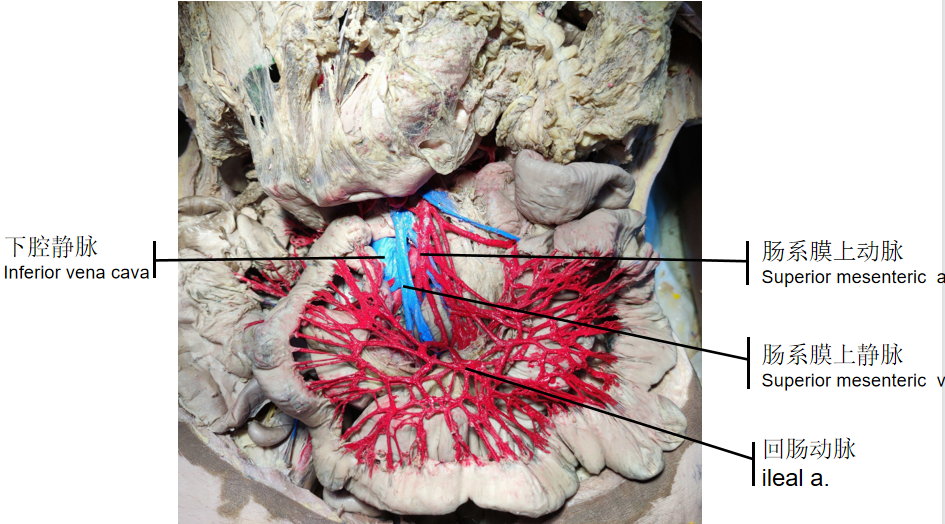

马文琪《肠系膜上动静脉的供血》